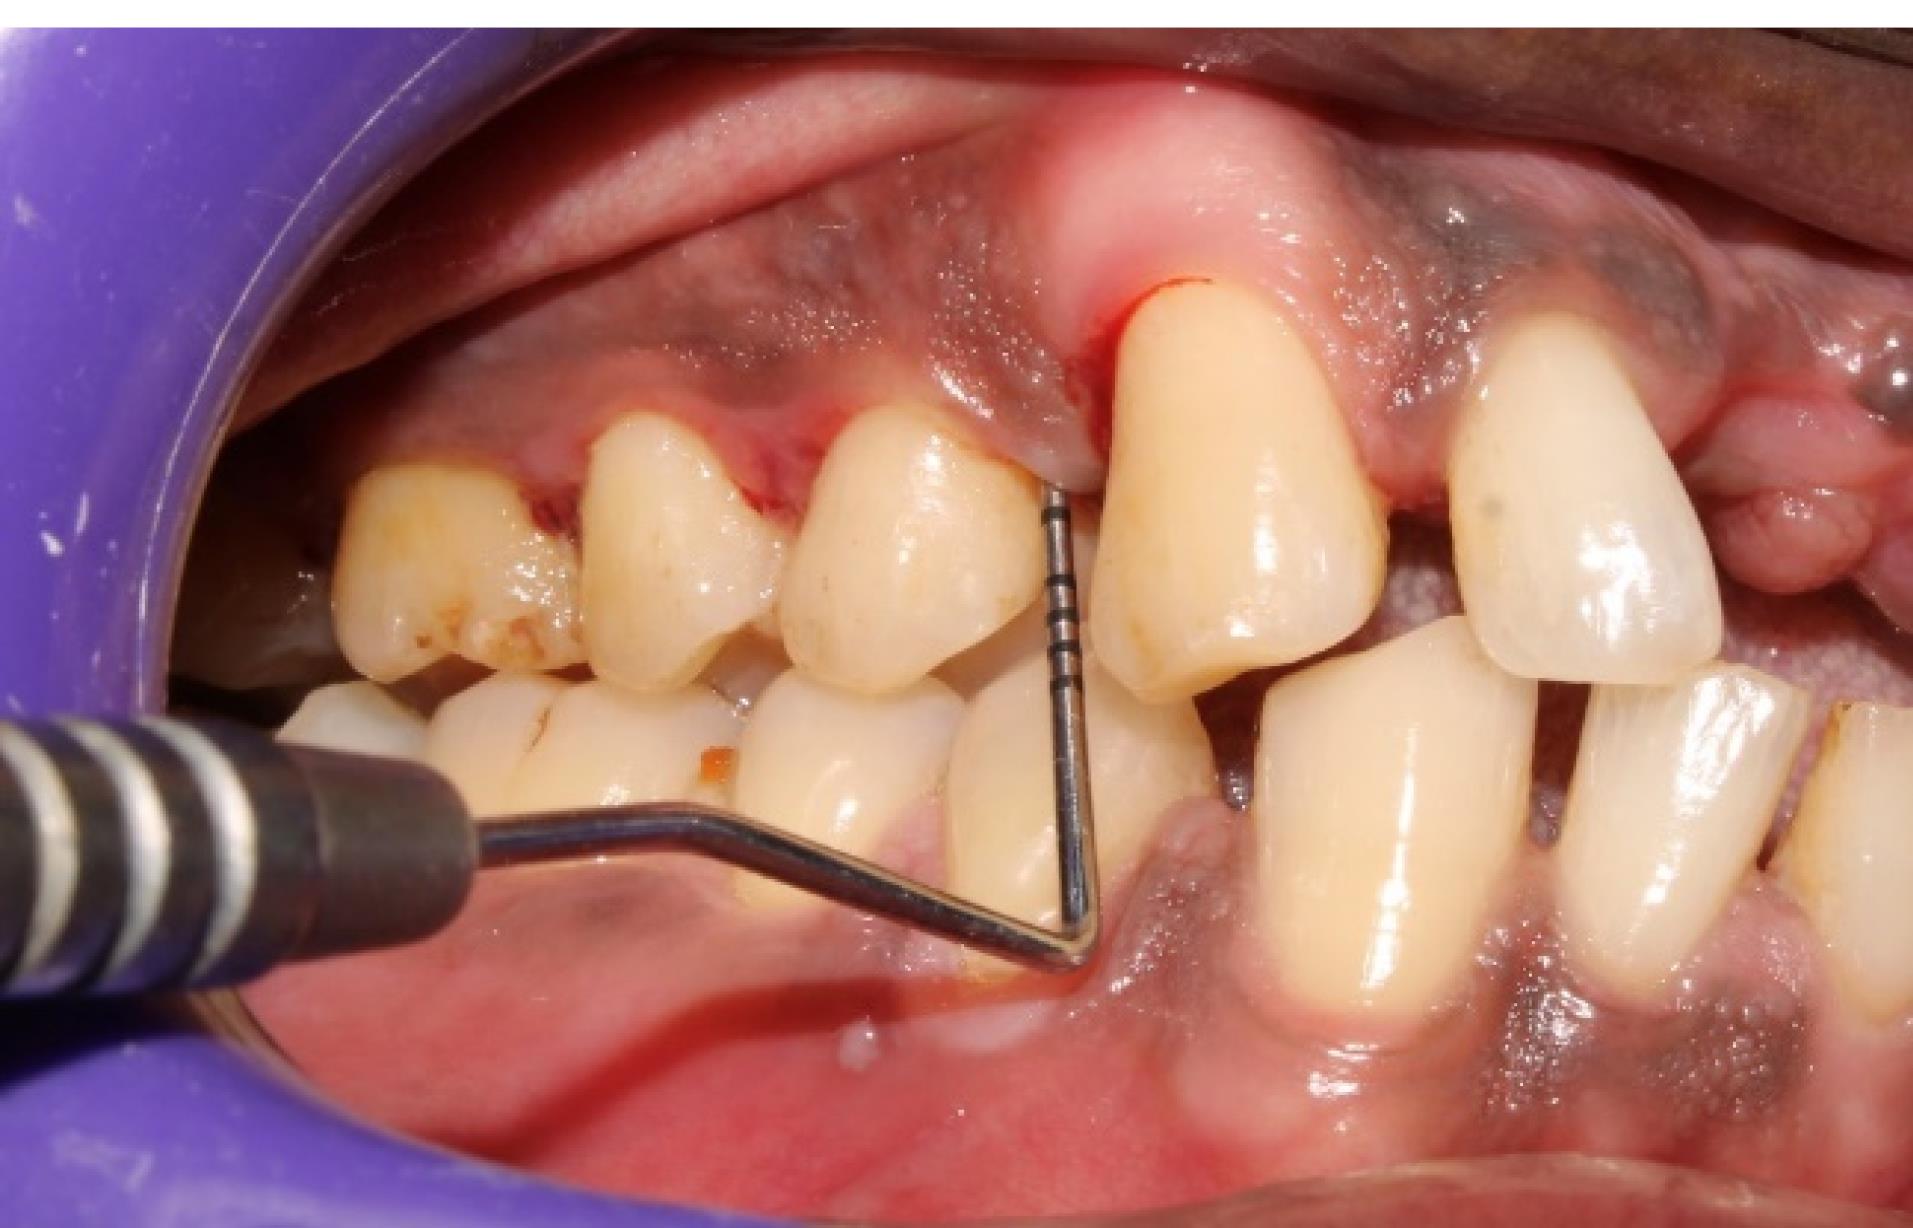

All the recruited subjects underwent the intervention (group 1 [n = 27], group 2 [n = 26], group 3 [n = 26]). During the follow-up, there were two dropouts from group 1 and one from each of the groups 2 and 3, resulting in 25 final samples in each group to be considered for final statistical analysis. No adverse reactions were observed during the study period for any of the interventions, and none of the participants reported any discomfort with the treatment protocol (Figures 5 and 6). The results are shown as mean ± standard deviation (SD) for clinical parameters and mean counts (log10) ± SD for microbiological parameters in Table 1 to Table 5.

Figure 5.

Preoperative picture (Baseline) showing PD in one of the experimental sites (#5) (group 1)